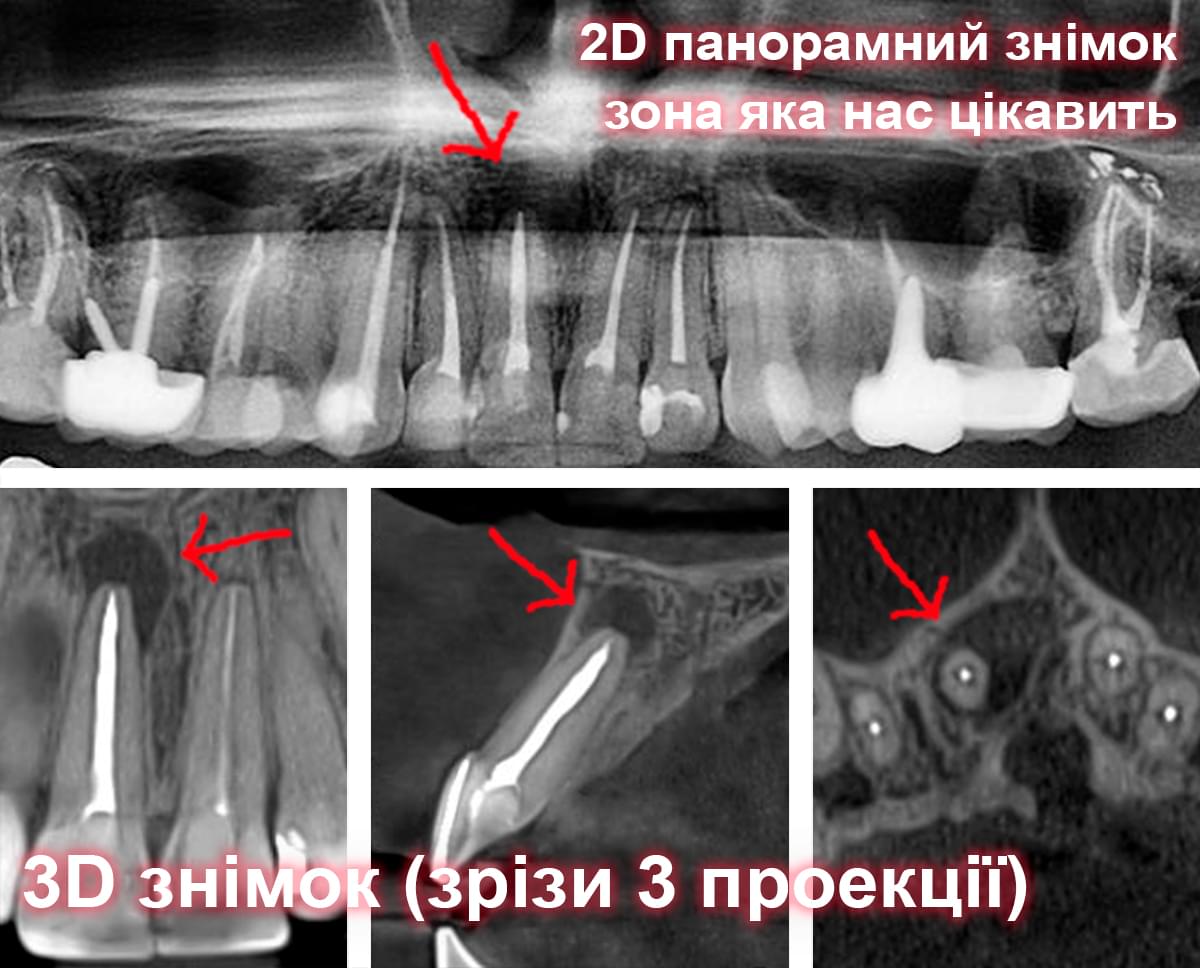

Візуальне порівняння (Кейс одного пацієнта)

Зуб — це не просто монолітний об'єкт, а складна система мікроканалів. На плоскому 2D-знімку вони часто перекривають один одного, створюючи ілюзію простої анатомії.

Непомічений канал — це джерело майбутньої інфекції та причина «загадкового» болю після лікування. Завдяки високій роздільній здатності обладнання MyRay, лікар бачить кожен мікронний канал ще до того, як візьме до рук інструмент.

Коли коріння «ховає сюрпризи» - Корені зубів часто мають складну кривизну, гачкоподібні закручення або розгалуження, які на звичайному 2D-знімку накладаються один на одного, створюючи ілюзію прямого каналу. На плоскій картинці неможливо побачити реальний об'єм та напрямок вигину, що критично важливо при видаленні «зубів мудрості» або ендодонтичному лікуванні. КТ MyRay дає змогу лікарю заздалегідь побачити 3D-геометрію кожного кореня, оцінити його близькість до нижньощелепного нерва чи гайморової пазухи та підібрати правильну тактику роботи. Це мінімізує ризики поломки інструменту в каналі або травмування сусідніх структур, перетворюючи складну хірургію на прогнозовану процедуру.